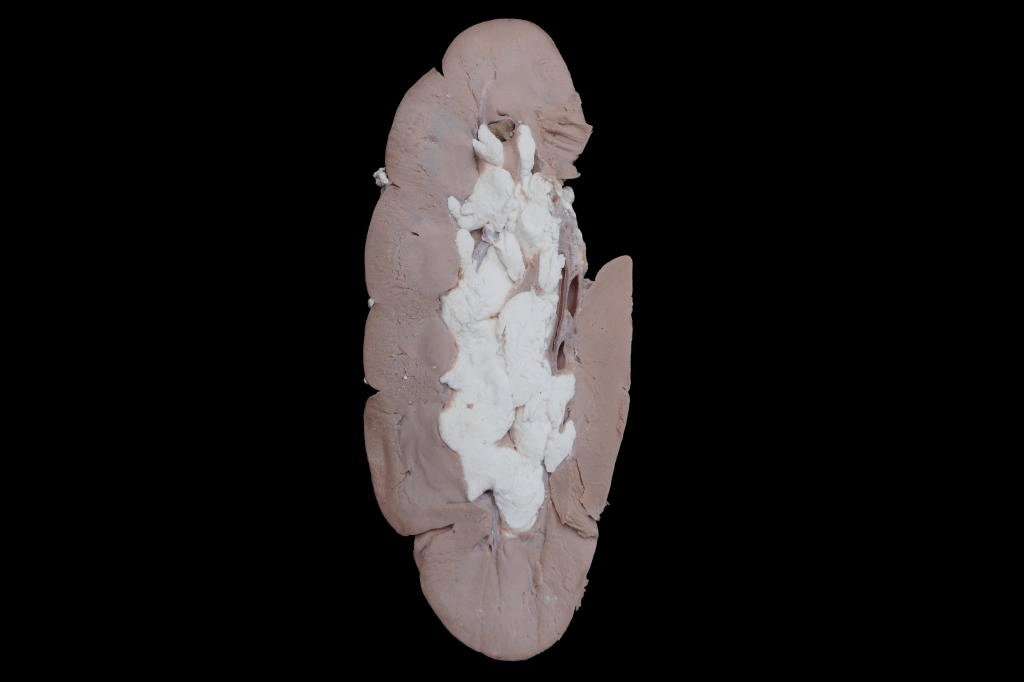

407肾结石